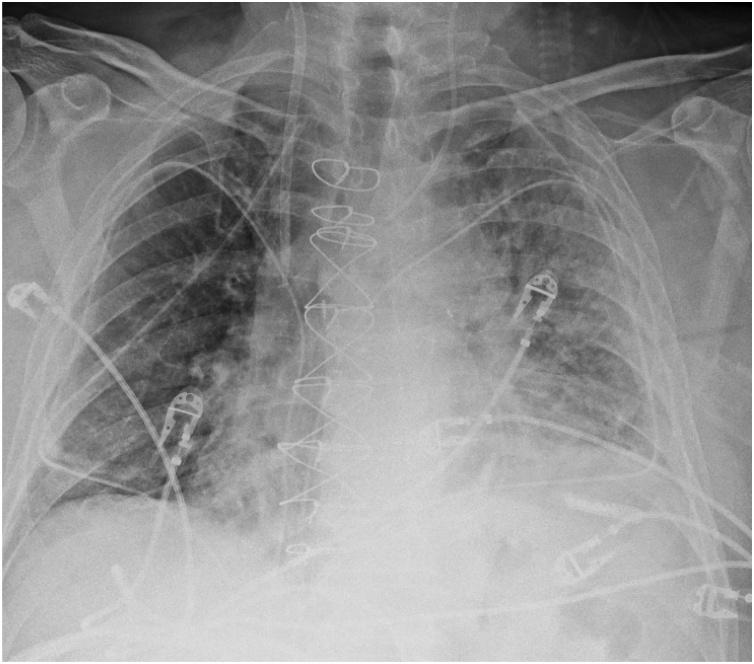

Pulmonary edema is a common clinical entity caused by the extravascular movement of fluid into the pulmonary interstitium and alveoli. The four physiologic categories of edema include hydrostatic pressure edema, permeability edema with and without diffuse alveolar damage (DAD), and mixed edema where there is both an increase in hydrostatic pressure and membrane permeability. As radiographic manifestations and etiologies are varied, an appreciation for both the common and uncommon manifestations and causes of pulmonary edema is essential for accurate diagnosis.

肺水肿是一种常见的临床病症,由液体向肺间质和肺泡的血管外移动所致。水肿的四种生理类型包括静水压性水肿、伴有或不伴有弥漫性肺泡损伤(DAD)的通透性水肿,以及静水压和膜通透性均增加的混合性水肿。由于影像学表现和病因各不相同,了解肺水肿的常见和不常见表现及病因对于准确诊断至关重要。